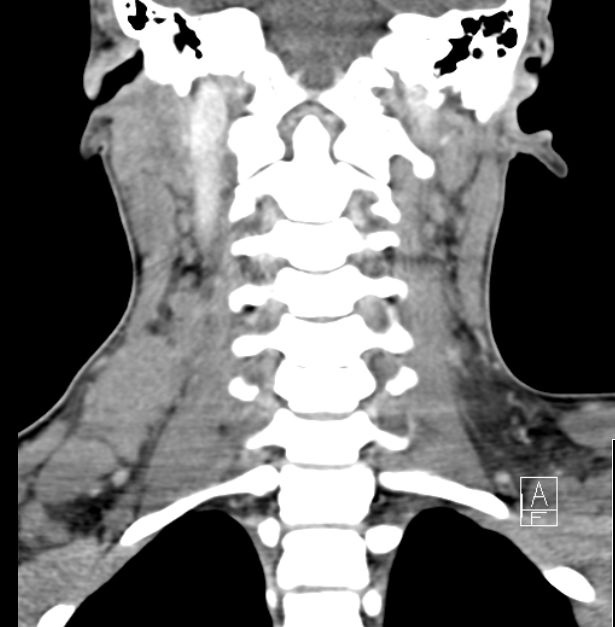

| Mediastinum | 30-jährige Frau therapieresistentem Husten. Das Röntgenbild zeigt eine Verbreiterung des oberen Mediastinums. Bronchoskopisch Impression der Trachea. Mediastinoskopische Biopsie: EBV-negatives klassisches Hodgkin-Lymphom. | ||